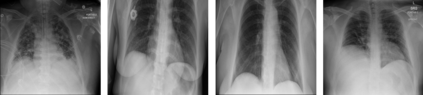

Medical image analysis continues to hold interesting challenges given the subtle characteristics of certain diseases and the significant overlap in appearance between diseases. In this work, we explore the concept of self-attention for tackling such subtleties in and between diseases. To this end, we introduce MEDUSA, a multi-scale encoder-decoder self-attention mechanism tailored for medical image analysis. While self-attention deep convolutional neural network architectures in existing literature center around the notion of multiple isolated lightweight attention mechanisms with limited individual capacities being incorporated at different points in the network architecture, MEDUSA takes a significant departure from this notion by possessing a single, unified self-attention mechanism with significantly higher capacity with multiple attention heads feeding into different scales in the network architecture. To the best of the authors' knowledge, this is the first "single body, multi-scale heads" realization of self-attention and enables explicit global context amongst selective attention at different levels of representational abstractions while still enabling differing local attention context at individual levels of abstractions. With MEDUSA, we obtain state-of-the-art performance on multiple challenging medical image analysis benchmarks including COVIDx, RSNA RICORD, and RSNA Pneumonia Challenge when compared to previous work. Our MEDUSA model is publicly available.